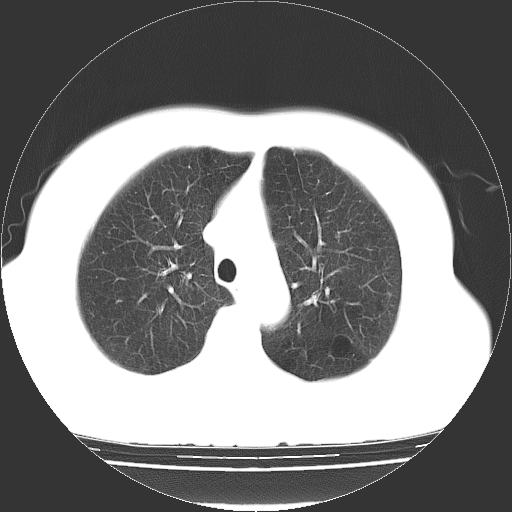

标题: CT13141:女,70岁,咳嗽、胸闷半个月。 [打印本页]

标题: CT13141:女,70岁,咳嗽、胸闷半个月。

女,70岁,咳嗽、胸闷半个月。纵隔窗未见异常,未上传。

慢性支气管炎合并小叶中心性肺气肿及间隔旁肺气肿.(多与吸烟有关)。

慢性支气管炎合并小叶中心性肺气肿,多发性肺大泡

慢性支气管炎并小叶中心性肺气肿及间隔旁肺气肿.(多与吸烟有关)。